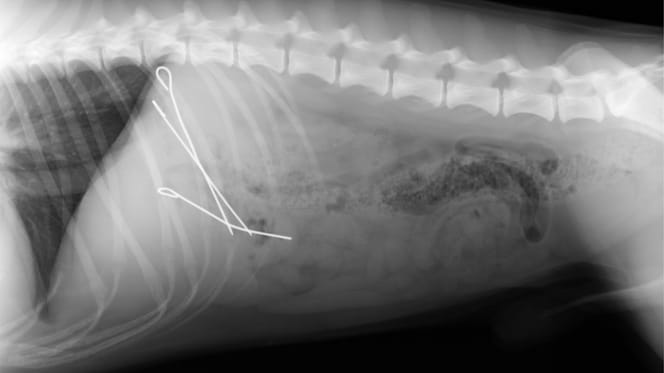

Röntgenbild eines Hundes mit Rouladennadeln

© Tierklinik Panitzsch / Facebook

Dort bringt moderne Technik schließlich Licht ins Dunkel. Als das Röntgenbild auf dem Monitor erscheint, gibt es keine Zweifel mehr. Die Aufnahme zeigt den Magen des „Diebes“ – und da sind selbst für Laien bestens erkennbar drei Rouladennadeln zu sehen.

Der Abend verlief für Herrchen, Frauchen und Hund somit „etwas anders als gedacht“, wie die Tierklinik auf Facebook am 25. Dezember 2025 berichtete. Denn schon wenig später folgt eine Not-OP, um die Metallspieße aus dem Hundebauch zu entfernen.